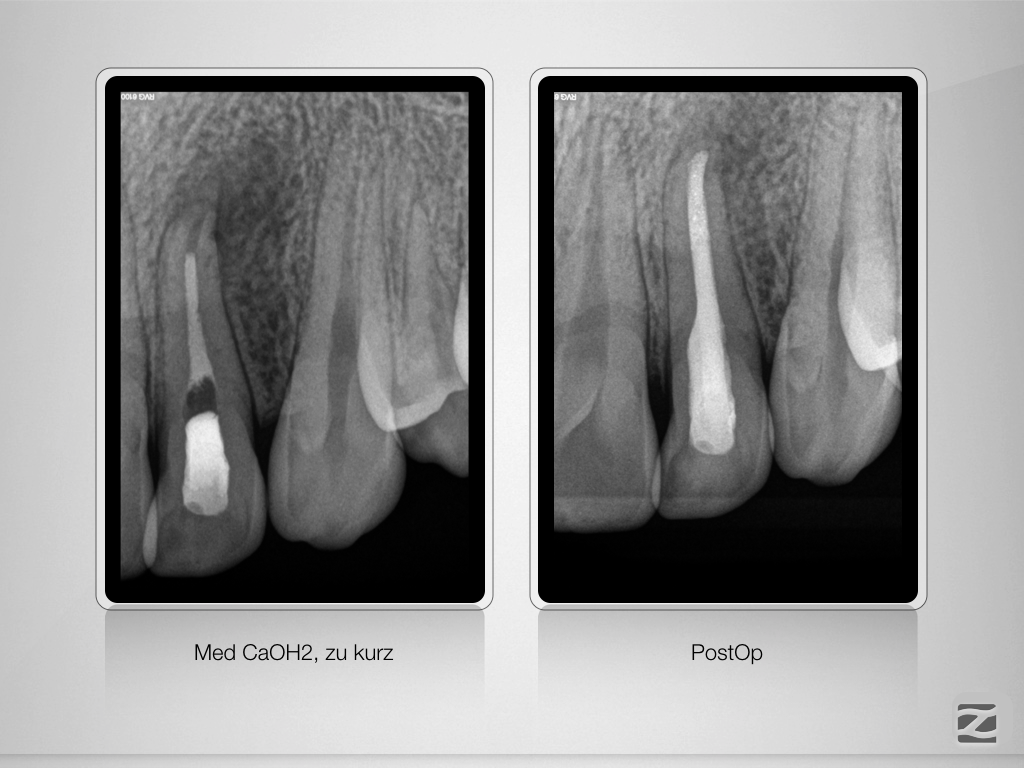

22D.012

Dens invaginatus